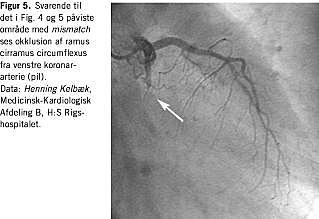

Ved den invasive undersøgelsesmetode koronarangiografi diagnosticeres stenoser/okklusioner af koronararteriernes grene, og eventuel kollateral blodforsyning kan erkendes visuelt (Figur 5 ). Undersøgelsen er indiceret hos alle patienter med angina pectoris, hvor medicinsk behandling er utilstrækkelig, og formentligt hos de fleste patienter med hjertesvigt. Selv om årsagen til hjertesvigtet er kendt, afslører koronarangiografi af og til udbredt koronar sygdom også hos patienter uden angina pectoris. Hvis årsagen til hjertesvigtet er iskæmisk hjertesygdom, er det væsentligt at få fastlagt, om der er indikation og mulighed for revaskularisering.